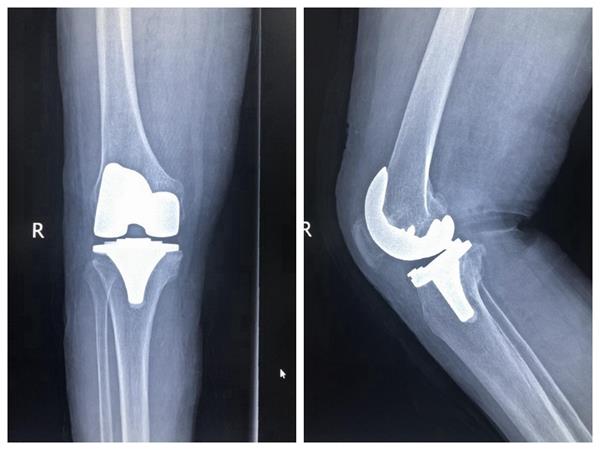

患者右膝關(guān)節(jié)術(shù)前、術(shù)后伸屈位放射影像

一位66歲的女性患者,右膝骨性關(guān)節(jié)炎終末期,經(jīng)過(guò)長(zhǎng)期保守治療無(wú)效,深受右膝病痛折磨,坐著輪椅由家人推著入住壽縣人民醫(yī)院骨科。科室主任劉本陽(yáng)組織醫(yī)師團(tuán)隊(duì)開(kāi)展討論,根據(jù)患者臨床表現(xiàn),結(jié)合多項(xiàng)檢查,確定人工膝關(guān)節(jié)置換為首選治療方法,并擇期手術(shù),為患者成功置換全膝人工膝關(guān)節(jié)。經(jīng)過(guò)精心治療護(hù)理,患者術(shù)后第四天下床活動(dòng),術(shù)后第七天出院回家康復(fù)休養(yǎng)。